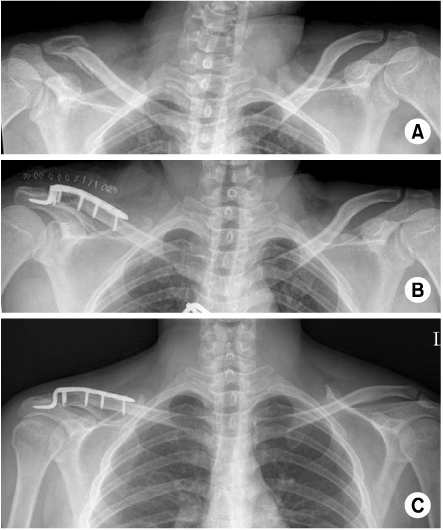

Fig. 1

(A) Preoperative radiograph of the left shoulder of a 55 year old male shows distal clavicle fracture.

(B) This is postoperative radiograph with Hook plate fixation.

(C) At 4 months follow-up, implant is removed without any complication. Bony union is achieved.

Fig. 1 (A) Preoperative radiograph of the left shoulder of a 55 year old male shows distal clavicle fracture. (B) This is postoperative radiograph with Hook plate fixation. (C) At 4 months follow-up, implant is removed without any complication. Bony union is achieved.